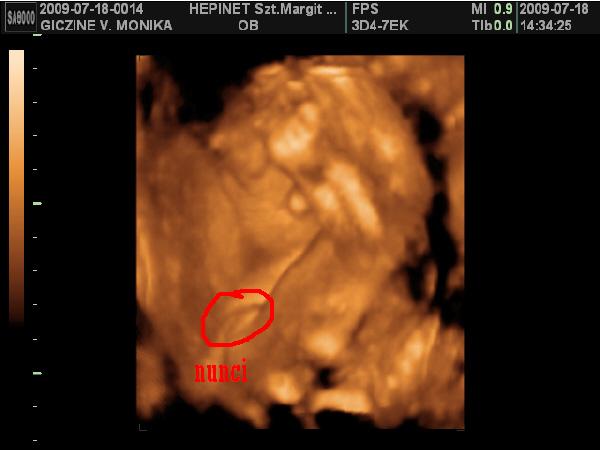

Lányok hoztam nektek képeket: :D :D

Kép

Ezek a képek szombaton készűltek. Bár nehéz volt jó képeket csinálni Lauráról, mert nagyon a méhlepény felé volt fordúlva. :D

Minden tökéletes vele, kb: 1 kilós már.

Ja!

És nagyon hasonlít a bátyjára. :lol: :lol: :lol:

Móni: jaj de édes a kis manó a képen :) és hogy látszik a puncija. jól beterpesztett :D

Gnemoni: nagyon édesek a képek, olyan szépen látszik a kis arcocskája. A nunci rendesen kivehető, igazán szépen beterpesztett megmutatta, hogy milyen van :lol: